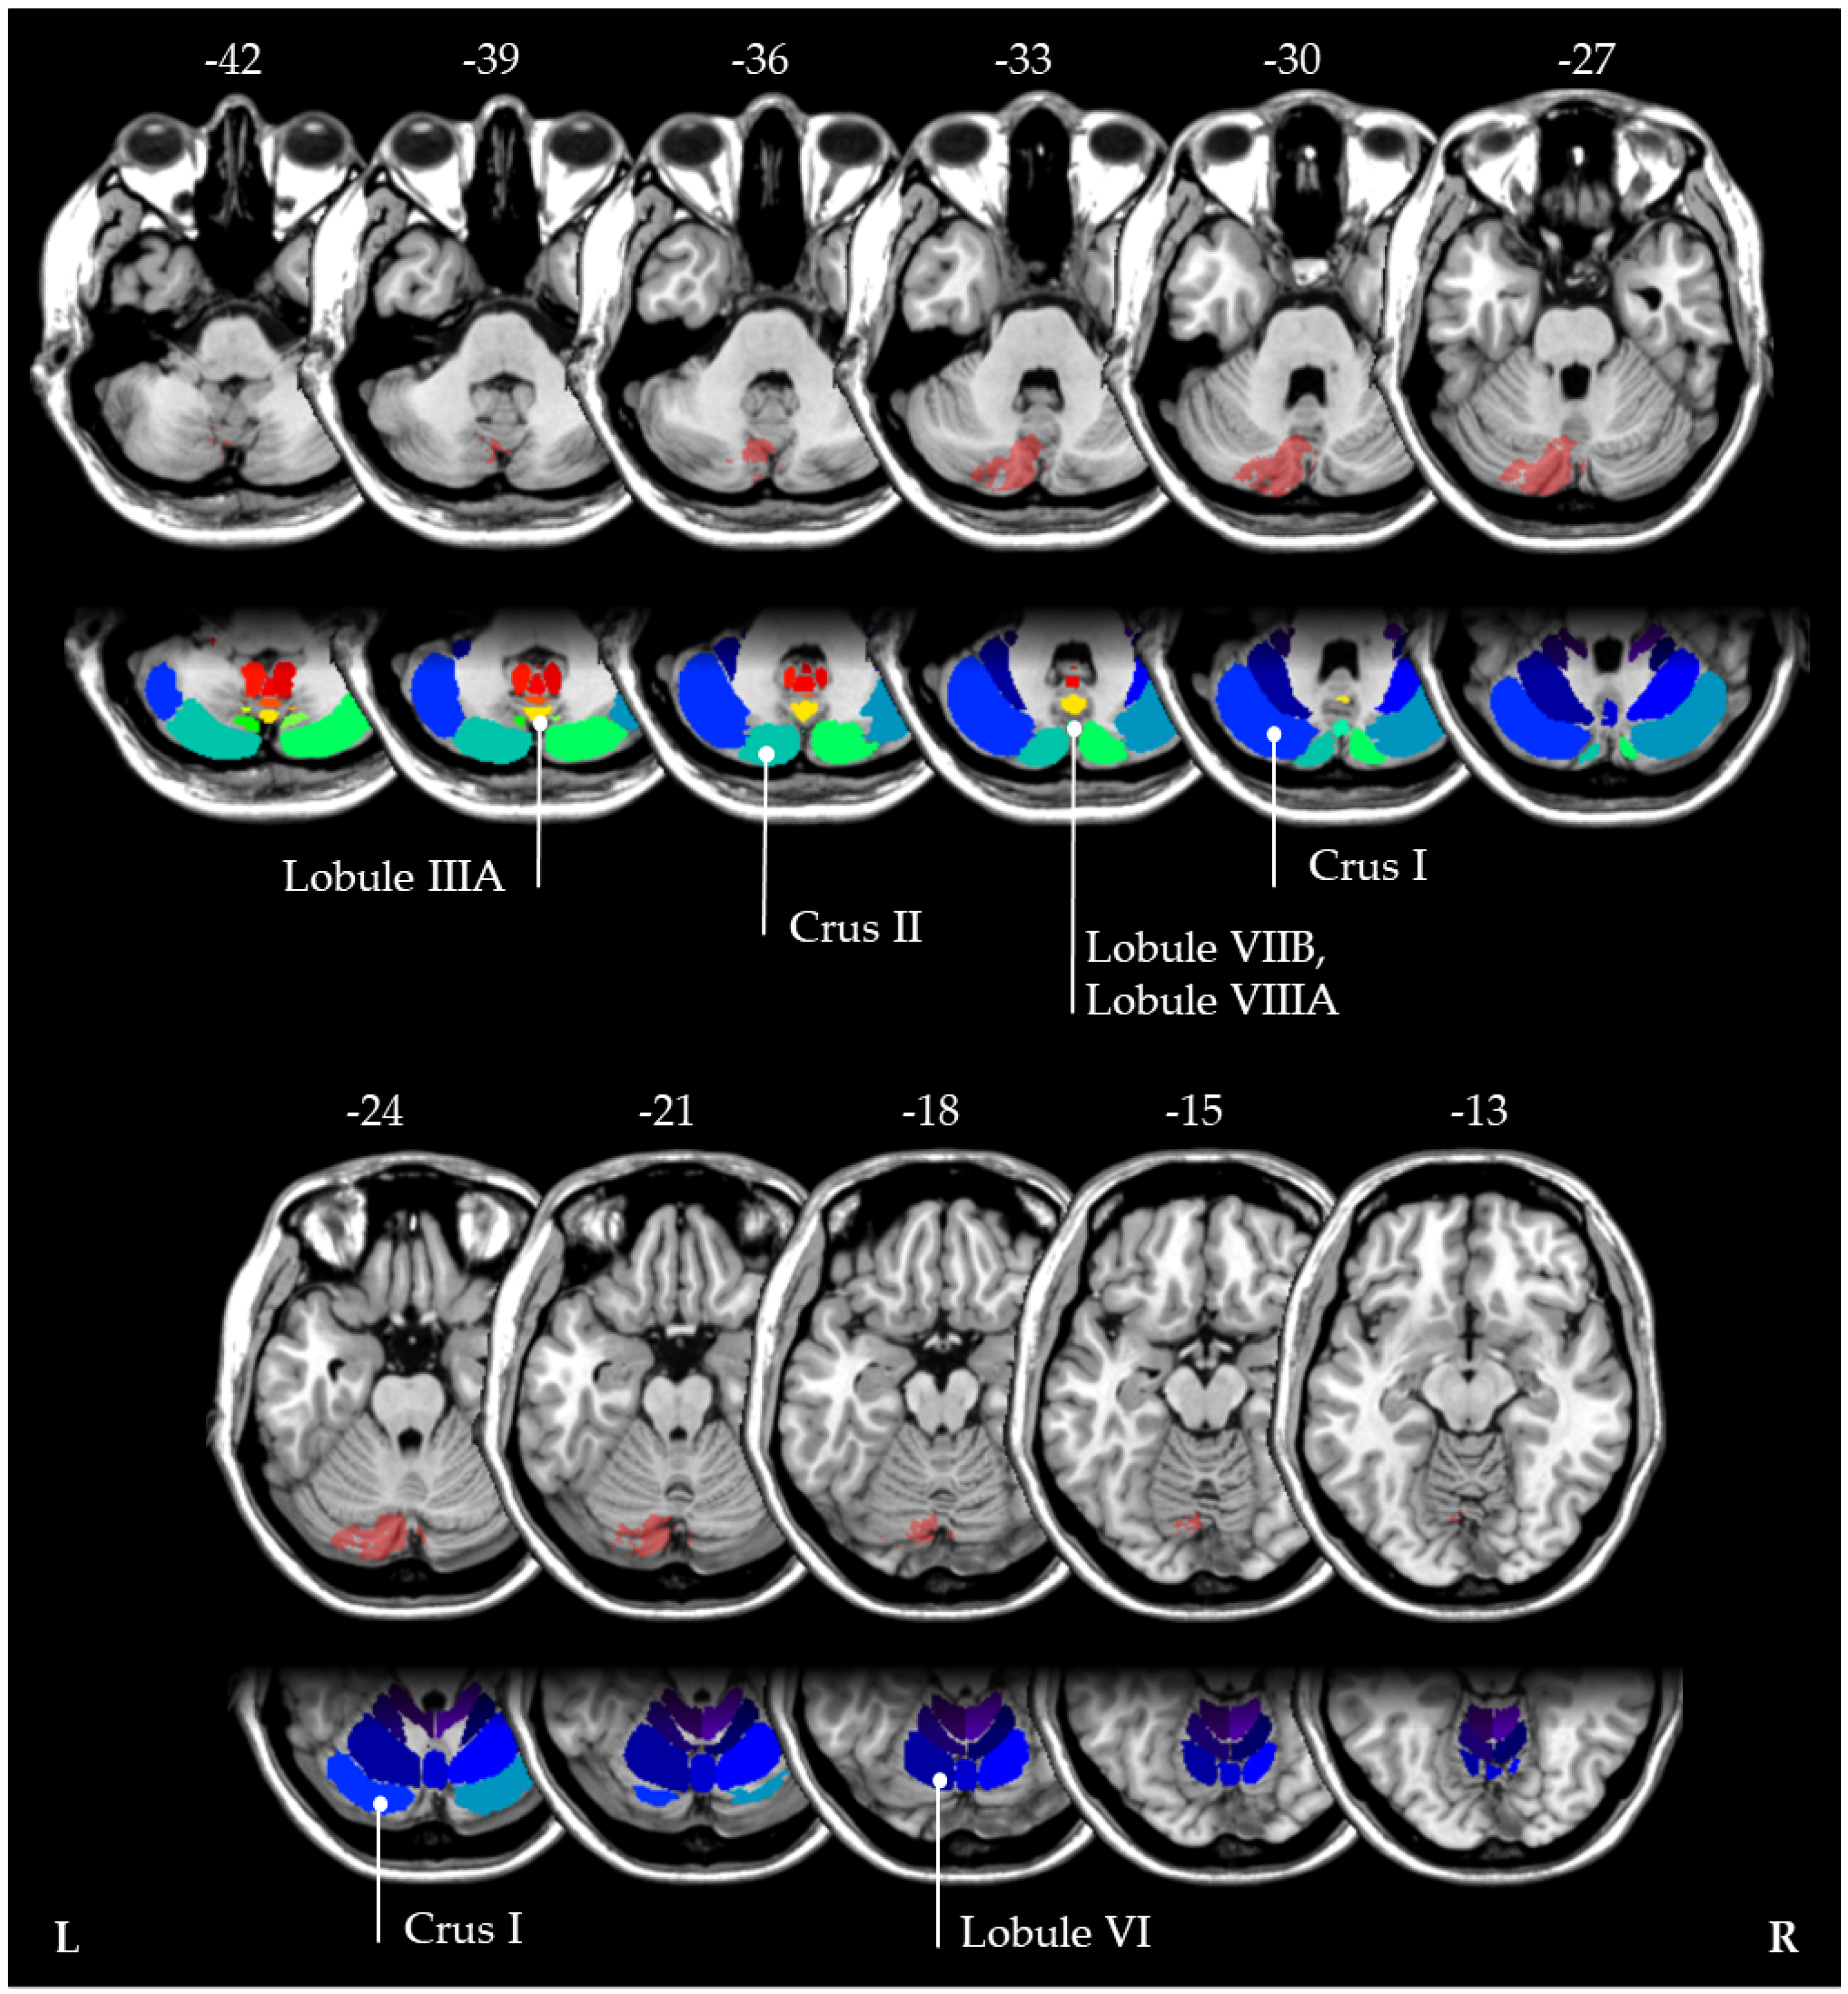

- Diedrichsen, J.; Balsters, J.H.; Flavell, J.; Cussans, E.; Ramnani, N. A probabilistic MR atlas of the human cerebellum. Neuroimage 2009, 46, 39–46. [Google Scholar] [CrossRef] [PubMed]